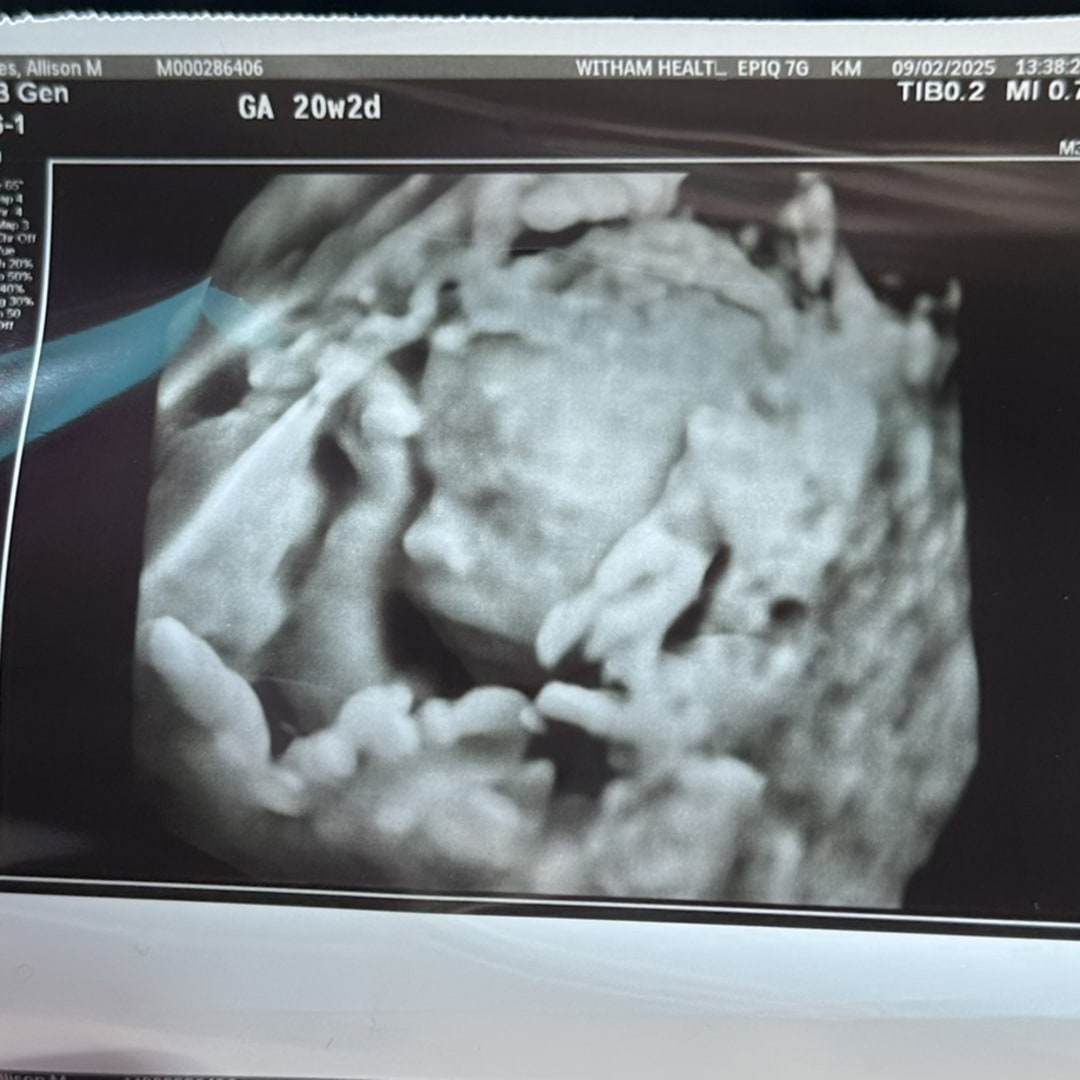

Rainbow Baby GIRL Hayes arriving in January. Thank you for everyone using our registry! We appreciate you all so much! 💕